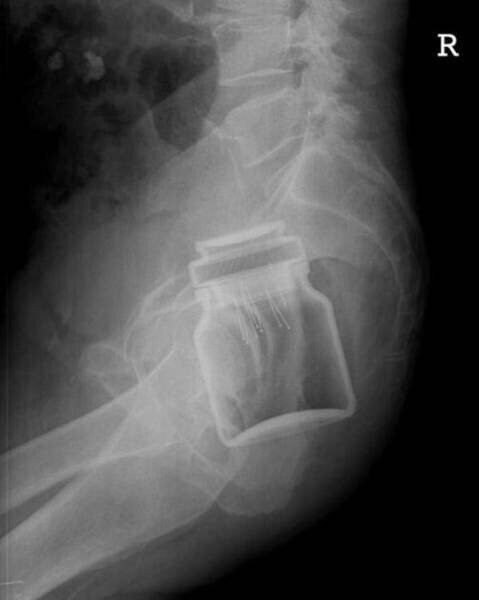

8. Банку з-під розчинної кави